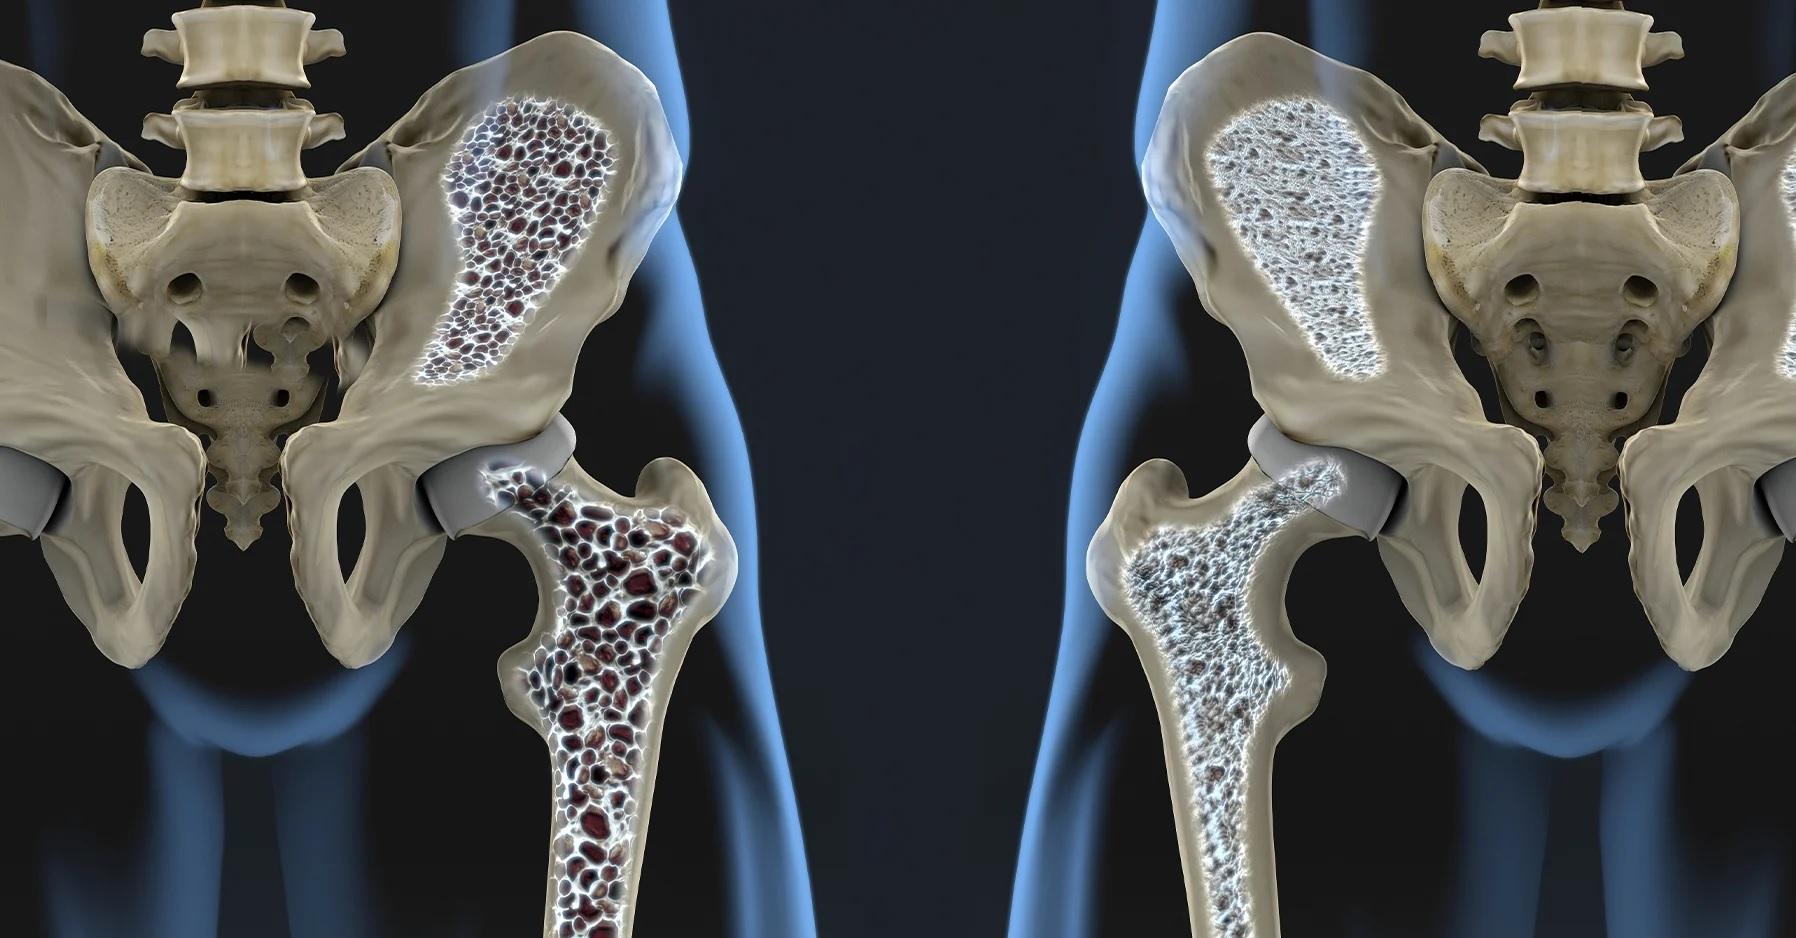

骨質疏鬆是高齡社會下最易被忽略的隱形殺手,尤其當跌倒後造成的骨質疏鬆骨折,又以髖部骨折最為嚴重,是導致長期臥床、行動受限,以及肌力萎縮的兇手,這類患者容易出現肺部及泌尿道感染,有極高的死亡風險。

仁愛長庚醫療聯盟大里仁愛醫院骨科部長黃贊文提醒,骨質疏鬆是值得關注的老年疾病,而年齡在75歲以上、有糖尿病或有柏金遜症、中風等長者,一旦跌倒所造成的髖關節骨折,更是危險。醫師警告,髖關節骨折後一年死亡率高達20%至30%,對於骨質疏鬆的預防與治療,必須及早介入。

黃贊文部長提醒,嚴重骨質疏鬆患者,應該優先使用促骨生成劑,快速拉高骨密度,改善骨頭品質,減少骨折發生風險,也能增加骨癒合改善背部疼痛,改善生活品質。

讓骨品質變好 是治療骨質疏鬆的效益之一

他提醒,嚴重骨質疏鬆患者,應該優先使用促骨生成劑,快速拉高骨密度,改善骨頭品質,減少骨折發生風險,也能增加骨愈合改善背部疼痛,改善生活品質。目前促骨生成劑也有生物相似藥可以使用,對於自費患者多了較可負擔的選擇。